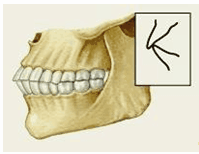

Рис.3. Схема прорезывания постоянного зуба, замещающего молочный . 1- эмаль, 2 -дентин, 3 - пульпа, 4 - остеокласты. Закладка постоянных зубов происходит в начале 5 мес внутриутробного развития. Зачаток постоянного ЗБ находится позади зачатка молочного. Когда прорезываются молочные ЗБ в зачатках постоянных происходит образование эмали и дентина. В процессе замены рост постоянного ЗБ и давление его эмали на корень молочного приводит к рассасыванию остеокластами более мягкой ткани - дентина молочного зуба. Последний выталкивается и заменяется постоянным. 3. Прикус Прикус (occlusio) — соотношение зубных рядов при наиболее плотном смыкании зубов. Смыкание зубов верхней и нижней челюстей при различных движениях последней называется окклюзией. Откусывание и прожевывание пищи сопровождаются различными видами окклюзий. Откусывание осуществляется при передней (сагиттальной) окклюзии, когда смыкаются передние зубы, а боковые разобщаются (между ними появляется просвет). При жевательных движениях возникают боковые (трансверзальные) правая и левая окклюзии. Исходным и заключительным положением для всех жевательных движений нижней челюсти являются центральная (вертикальная) окклюзия, при которой линия, проходящая между центральными резцами обоих зубных рядов, совпадает со срединной линией лица. Вид П. определяется характером смыкания зубных рядов в положении центральной окклюзии, что зависит от формы и размеров зубов, их количества и места в зубных рядах, а также от размеров челюстных костей и их положения. В норме понятия «прикус» и «центральная окклюзия» почти идентичны, т. е. прикусом считают соотношение зубных рядов в состоянии центральной окклюзии. Нормальный, или физиологический, П. характеризуется определенными признаками. Все зубы верхней и нижней челюстей (за исключением третьего верхнего моляра и первого нижнего резца) контактируют между собой таким образом, что каждый зуб смыкается с двумя антагонистами. Каждый зуб верхней челюсти контактирует с одноименным и позадистоящим зубом нижней челюсти, каждый зуб нижней челюсти — с одноименным впереди стоящим зубом верхней челюсти; срединная линия лица проходит между центральными резцами верхней и нижней челюстей и находится с ними в одной сагиттальной плоскости. В зубных рядах промежутки между зубами отсутствуют. Зубные дуги имеют определению форму (верхняя — полуэллипса, нижняя — параболы). Наружная часть верхней зубной дуги больше внутренней части за счет наклона зубов в сторону преддверия рта. наружная часть нижней зубной дуги меньше внутренней части за счет наклона зубов в сторону полости рта. При смыкании зубных рядов формируется окклюзионная кривая. Суставная головка нижней челюсти находится в середине суставной ямки височно-нижнечелюстного сустава. Различают несколько вариантов нормального П. (ортогнатический, прогенический, прямой, бипрогнатический). Они характеризуются смыканием зубных рядов на всем протяжении и отличаются друг от друга лишь особенностями смыкания функционально ориентированных групп зубов, в частности передних. Эталонным принято считать ортогнатический прикус (рис. 5, а), при котором верхний зубной ряд на всем протяжении перекрывает нижний, а во фронтальном участке верхние резцы перекрывают нижние не более чем на 1 /3 коронковой части зуба; между резцами верхней и нижней челюстей имеется режуще-бугорковый контакт. Прогенический прикус (рис. 5, б) отличается умеренным выстоянием нижнего зубного ряда. Прямой прикус (рис. 5, в) характеризуется тем, что верхние резцы не перекрывают нижние, а смыкаются режущими краями. При бипрогнатическом прикусе (рис. 5, г) верхние и нижние резцы наклонены в сторону преддверия рта, но между ними сохранен режуще-бугорковый контакт. Для всех вариантов нормального прикуса обязательным условием является нормальное функционирование зубочелюстной системы. Патологический П. формируется при аномалиях зубов и челюстей врожденного или приобретенного характера (пародонтоз, пародонтит и др.). Основным отличием патологического прикуса от нормального является нарушение смыкания зубных рядов в различных направлениях вплоть до полного отсутствия на отдельных участках, что приводит к изменению функции зубочелюстной системы. Существует множество классификаций аномалий П., однако общепринятой является международная классификация, предложенная в 1899 г. Энглом (Е.Н. Angle). В ее основе лежит соотношение первых моляров, что, по мнению Энгла, служит ключом окклюзии. В соответствии с классификацией к первому классу (рис. 6, а) относятся все аномалии, при которых первые моляры находятся в правильном соотношении (мезиально-шеечный бугор первого моляра верхней челюсти располагается в межбугорковой фиссуре первого моляра нижней челюсти), а все аномалии П. обусловлены изменениями зубов или челюстей спереди от первых моляров, например при скученности резцов, их протрузии (наклоне в сторону преддверия рта) или ретрузии (наклоне в сторону полости рта). Во второй класс включены аномалии, при которых нарушено смыкание первых моляров и фронтальной группы зубов. Межбугорковая фиссура первого моляра нижней челюсти располагается позади мезиально-щечного бугра первого моляра верхней челюсти, т.е. нарушено смыкание зубов в сагиттальной плоскости (переднезаднем направлении). Подобные нарушения (так называемый дистальный прикус) могут быть обусловлены чрезмерным ростом верхней челюсти (прогнатией) или (реже) недоразвитием нижней челюсти (микрогенией). В зависимости от положения и смыкания фронтальной группы зубов во втором классе выделяют два подкласса: первый характеризуется протрузией резцов (рис. 6, б), второй — их ретрузией (рис. 6, в). Третий класс (рис. 6, г) включает аномалии П., при которых межбугорковая фиссура первого моляра нижней челюсти располагается впереди мезиально-щечного бугра одноименного моляра верхней челюсти (мезиальный П., прогения, прогенический П., антериальный П.). Кроме аномалий П. в сагиттальной плоскости существуют аномалии П. в вертикальной и трансверзальной плоскостях. К основным вертикальным аномалиям (определяются по отношению к горизонтальной плоскости) относится открытый и глубокий П. Открытый П. (рис. 7, а) — наличие щели между зубными рядами при их смыкании, чаще в области передних зубов, реже в области боковых. Иногда смыкаются только последние моляры, что приводит к выраженным нарушениям жевательной функции и особенно речи. При глубоком П. (рис. 7, б) передние зубы одной из челюстей в значительной степени перекрывают коронки зубов-антагонистов, нижние резцы не опираются на зубные бугорки верхних резцов, а соскальзывают к их десневому краю, что приводит к постоянному травмированию десен и неба; нижняя часть лица укорочена за счет уменьшения или дистального положения подбородка. К трансверзальным аномалиям, определяемым по отношению к сагиттальной плоскости, относится перекрестный П. (рис. 7, в), при котором верхний зубной ряд в области боковых участков в значительной степени перекрывает нижний зубной ряд (латерогнатический П.) или нижний перекрывает верхний (латерогенический П.). Кроме перечисленных выше видов патологического П. выделяют так называемый снижающийся прикус, который формируется вследствие стирания зубов или их утраты. При этом нижняя треть лица укорочена, расстояние между зубами увеличено (до 8—10 мм при норме 2—3 мм), углы рта опущены, носогубные складки резко выражены. При потере боковых зубов в детском или юношеском возрасте возможно дистальное смещение нижней челюсти. Снижающийся П., как правило, приводит к изменению соотношения элементов височно-нижнечелюстного сустава, в результате чего могут возникать боли в области сустава, затруднения и асимметрия движений нижней челюсти, щелканье или треск в суставе при его движениях, головные боли, шум в ушах. Патологический П., возникший при уже сформировавшемся нормальном П. в результате заболеваний или утраты зубов, как правило, сопровождается деформацией зубных рядов, смещением отдельных зубов или их групп, иногда вместе с альвеолярным отростком. Аномалии П. определяются при осмотре полости рта. Причину формирования аномалии устанавливают после изучения формы и размеров зубов, зубных рядов, апикальных базисов челюстей с помощью гипсовых моделей челюстей. Размеры челюстных костей и их положение в черепе определяют с помощью телерентгенографии, размеры и формы височно-нижнечелюстных суставов — с помощью томографии. Большое значение имеют функциональные методы исследования мышц челюстно-лицевой области (электромиография, миотонометрия), пародонта (гнатодинамометрия, периотестометрия), височно-нижнечелюстных суставов (аксиография, фонография). Для исправления аномалий П. применяют ортодонтические методы лечения, направленные на изменение формы и нормализацию размеров зубных рядов, их соотношения и окклюзии. При резко выраженных аномалиях П. наряду с ортодонтическими методами применяют и оперативное лечение. При стирании или потере зубов показано протезирование. Лечебные мероприятия при аномалиях прикуса целесообразно начинать как можно раньше с момента их выявления. Большое значение для формирования правильного П. у детей и сохранения его у взрослых имеют профилактические мероприятия, к которым относится выявление детей из групп риска (дети с врожденной патологией или неблагоприятной наследственностью, нарушением носового дыхания и др.), полноценное питание и правильный режим матери в период беременности, введение своевременного при корма, предупреждение рахита и других заболеваний у ребенка, устранение вредных привычек (сосание пальца, языка, щек). Особое место занимают своевременное лечение зубов и восстановление целостности зубных рядов путем их протезирования. В связи с тем что наиболее часто зубочелюстные аномалии возни кают в период смены зубов, дети от 6 до 13 лет нуждаются в особенно тщательном наблюдении.

Рис. 5а). Схематическое изображение челюстей при основных разновидностях нормального прикуса (вид сбоку): ортогнатический прикус.

Рис. 5б). Схематическое изображение челюстей при основных разновидностях нормального прикуса (вид сбоку): прогенический прикус.

Рис. 5в). Схематическое изображение челюстей при основных разновидностях нормального прикуса (вид сбоку): прямой прикус.

Рис. 5г). Схематическое изображение челюстей при основных разновидностях нормального прикуса (вид сбоку): бипрогнатический прикус.